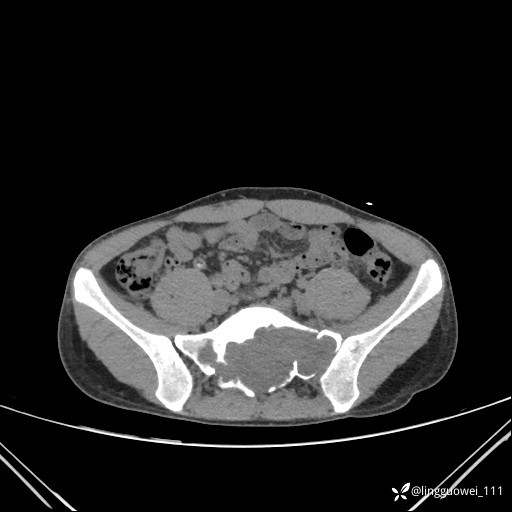

男,25岁,腰痛4年,加重左下肢痛5天,先上传X光片,第2天再上传CT。MR

动脉期:

静脉期: